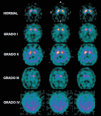

Fig. 1. En la fila superior se observan 3 cortes transversales de una tomografía computarizada por emisión de fotón único con #123#I-FP-CIT que muestran una captación homogénea en los núcleos de la base. Se delimitan claramente las estructuras del núcleo caudado (más anteriores y redondeadas) y del putamen, que se adelgaza hacia su porción más posterior. Grado I: captación disminuida unilateral en el putamen derecho; grado II: captación disminuida bilateral; grado III: captación disminuida bilateral y muy asimétrica; grado IV: ausencia de captación de los núcleos de la base.A: anterior; P: posterior; D: derecha; I: izquierda.